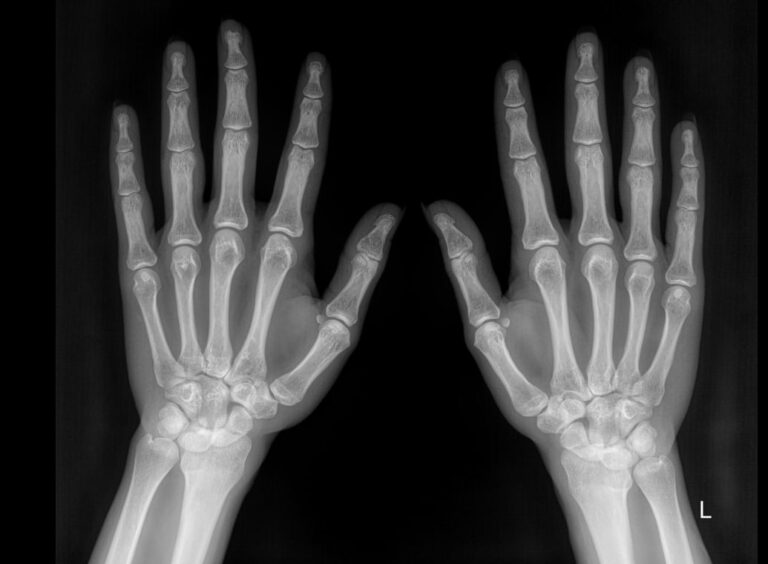

Рентген костей и суставов ― стандартная диагностическая процедура. Она основана на проникающей способности рентгеновского излучения, которое по разному задерживается в тканях разной плотности. Соответственно, изображение тканей на снимке будет в виде пятен также разных оттенков серого, от белого до практически черного. Как наиболее плотные, кости визуализируются как самые яркие. Современная аппаратура испускает минимальное излучение, составляющее минимальную часть от предельно допустимой годовой дозы.

Хронические системные патологии обычно поражают дистальные отделы верхних конечностей одновременно. Именно для этого и требуется снимок обеих кистей. В случае травмы или выявления врожденной аномалии рентгенограмма двух рук необходима для сравнения анатомических особенностей.